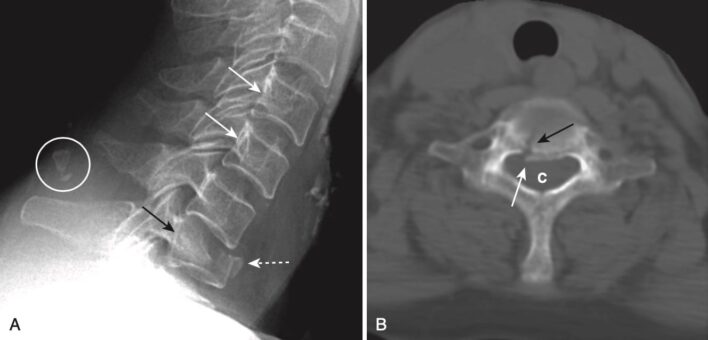

Gãy vỡ nhiều mảnh (burst)

- Gãy vỡ nhiều mảnh có thể xảy ra ở bất kỳ đoạn nào nhưng thường gặp nhất là ở cột sống cổ, cột sống ngực và cột sống thắt lưng trên.

- Đó là những chấn thương do lực tải dọc trục nặng nề (năng lượng cao), thường thứ phát sau tai nạn xe cơ giới hoặc ngã, trong đó đĩa đệm ở trên bị dồn vào thân đốt sống bên dưới, và thân đốt sống bị vỡ ra. Điều này làm cho các mảnh xương bị đẩy ra phía sau vào ống sống (các mảnh xương lồi ra sau), và mặt trước của thân đốt sống bị di lệch ra phía trước.

- Bởi vì những gãy xương này liên quan đến sự xâm nhập vào ống sống, phần lớn gãy vỡ nhiều mảnh này kèm theo khiếm khuyết thần kinh.

- Các dấu hiệu của gãy vỡ nhiều mảnh bao gồm gãy nén ép nhiều mảnh (comminuted compression fracture) của thân đốt sống, trong đó phần sau của thân đốt bị đẩy ra phía sau về phía ống sống. CT là thăm dò hình ảnh tốt nhất để xác định các mảnh xương trong ống sống (Hình 17).